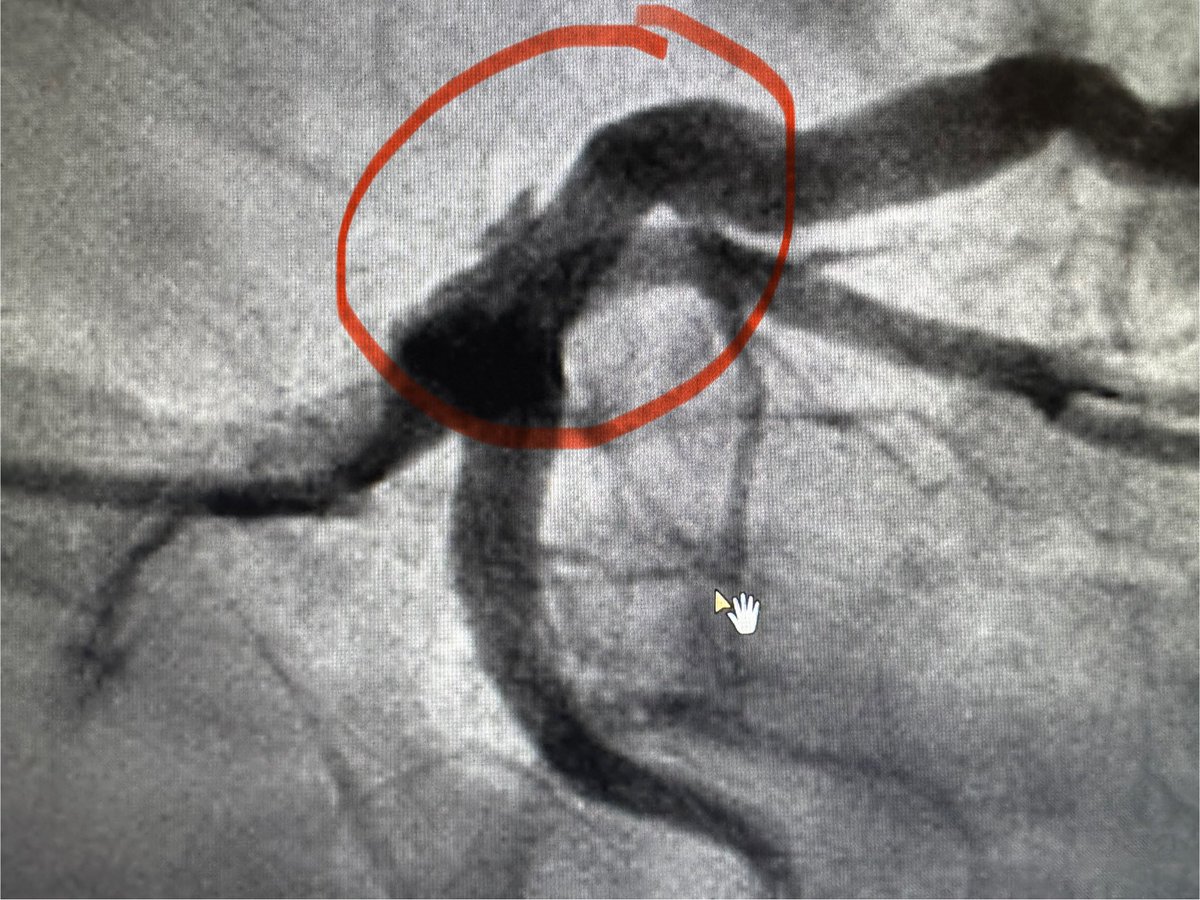

🔹How would you manage this ostial LCx stenosis? #FFR = 0.70 after IC adenosine. Large dominant LCx. No other significant disease. Severe angina despite OMT. #CardioTwitter #ACCIC @BifurcationClub #ACCFIT #Cardiology